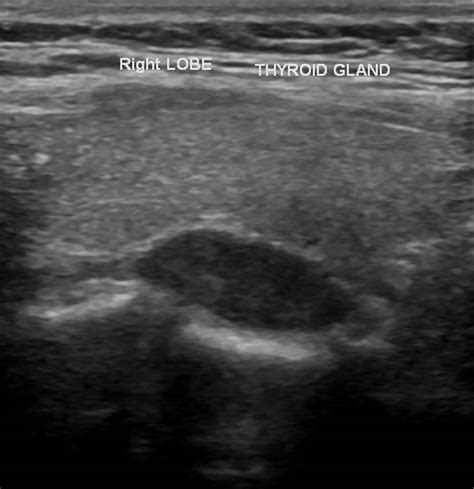

• Presence of any nodules or masses.

• Location of the parathyroid glands relative to the thyroid gland.

Abnormal findings may include enlarged parathyroid glands, the presence of adenomas, or other structural abnormalities. These findings are crucial for diagnosing conditions such as primary hyperparathyroidism, secondary hyperparathyroidism, and parathyroid carcinoma.

Parathyroid Adenomas Benign tumors within the parathyroid glands. Primary Hyperparathyroidism